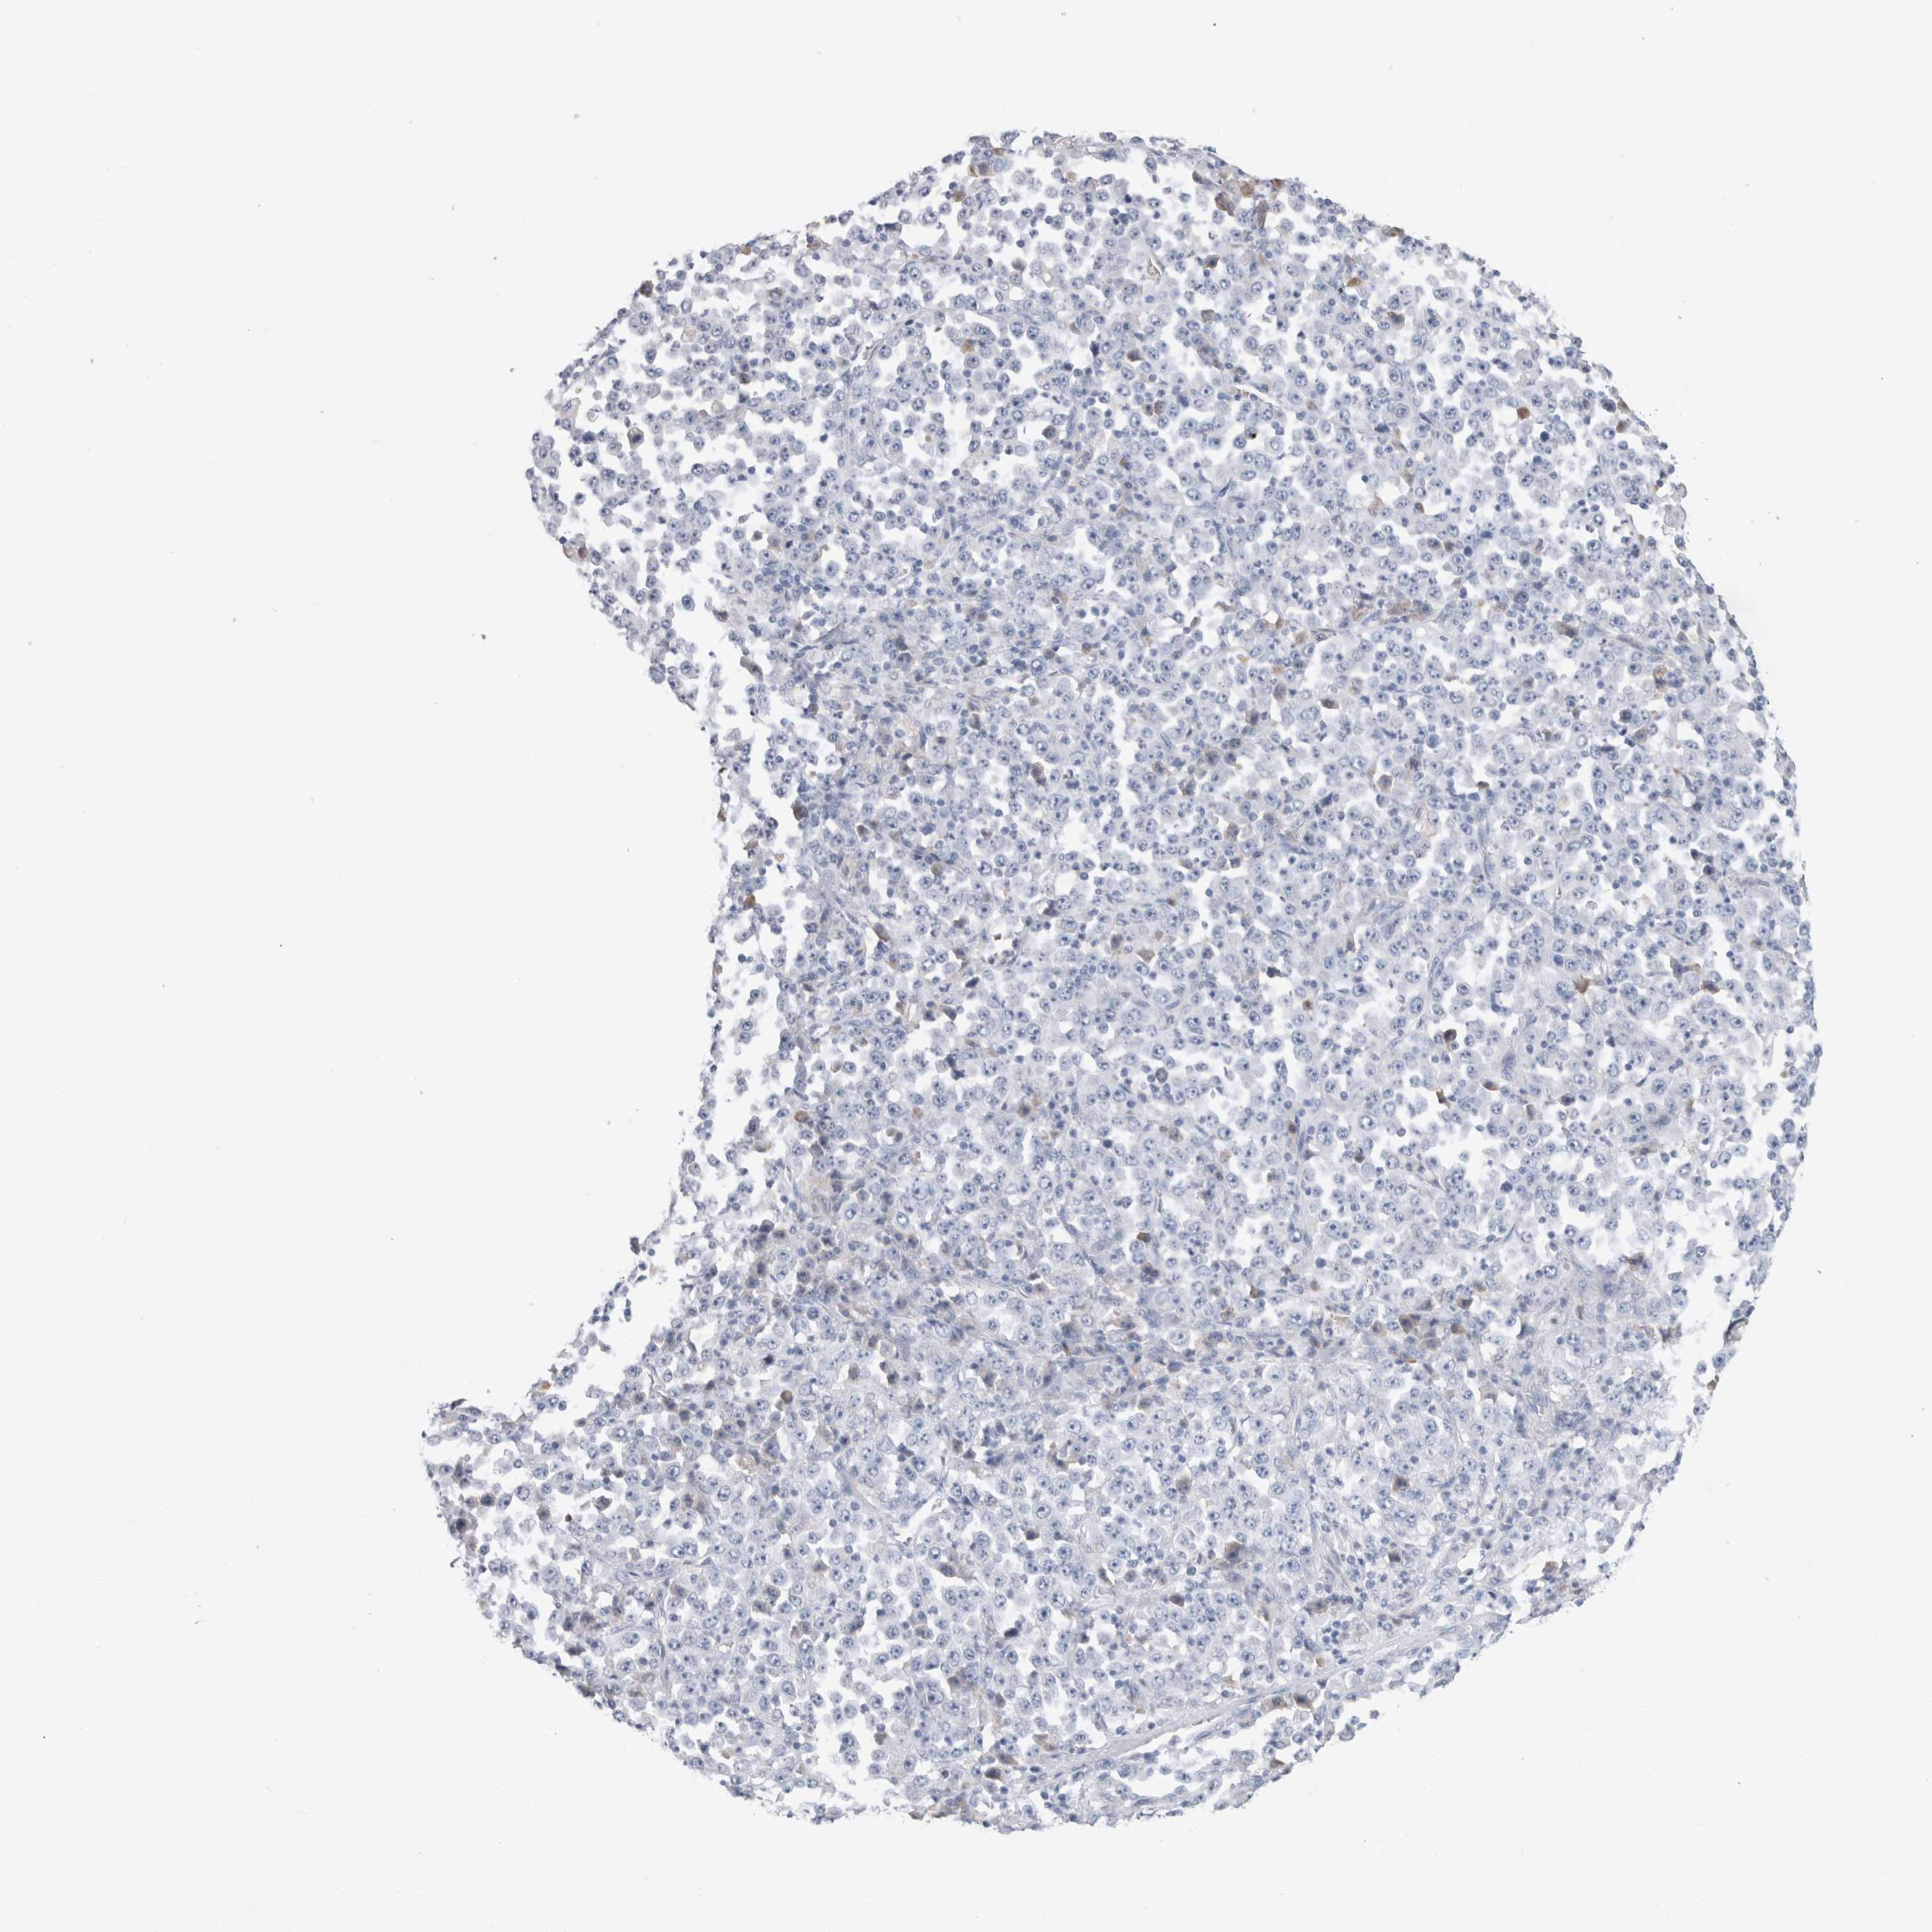

STOMACH CANCER - Protein expressioni

A mouse-over function shows sample information and annotation data. Click on an image to view it in a full screen mode. Samples can be filtered based on level of antibody staining by selecting one or several of the following categories: high, medium, low and not detected. The assay and annotation is described here.

Antibody stainingi

Antibody staining in the annotated cell types in the current human tissue is reported as not detected, low, medium, or high, based on conventional immunohistochemistry profiling in selected tissues. This score is based on the combination of the staining intensity and fraction of stained cells.

Each image is clickable and will lead to virtual microscopy that enables deeper exploration of all samples and also displays staining intensity scores, fraction scores and subcellular localization as well as patient and tissue information for each sample.

Antibody HPA031828

Antibody CAB025686

Staining

High

Medium

Low

Not detected

Intensity

Strong

Moderate

Weak

Negative

Quantity

>75%

75%-25%

<25%

None

Location

Nuclear

Cytoplasmic/membranous

Cytoplasmic/membranous,nuclear

Adenocarcinoma, NOS

Adenocarcinoma, High grade